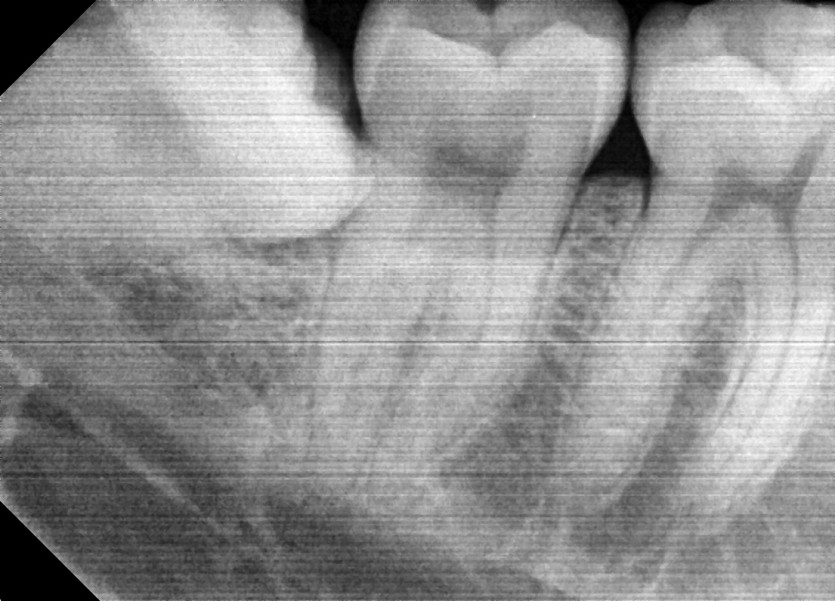

#18,48 사랑니 발치

구강 외과 전문의가 당일 발치했습니다.